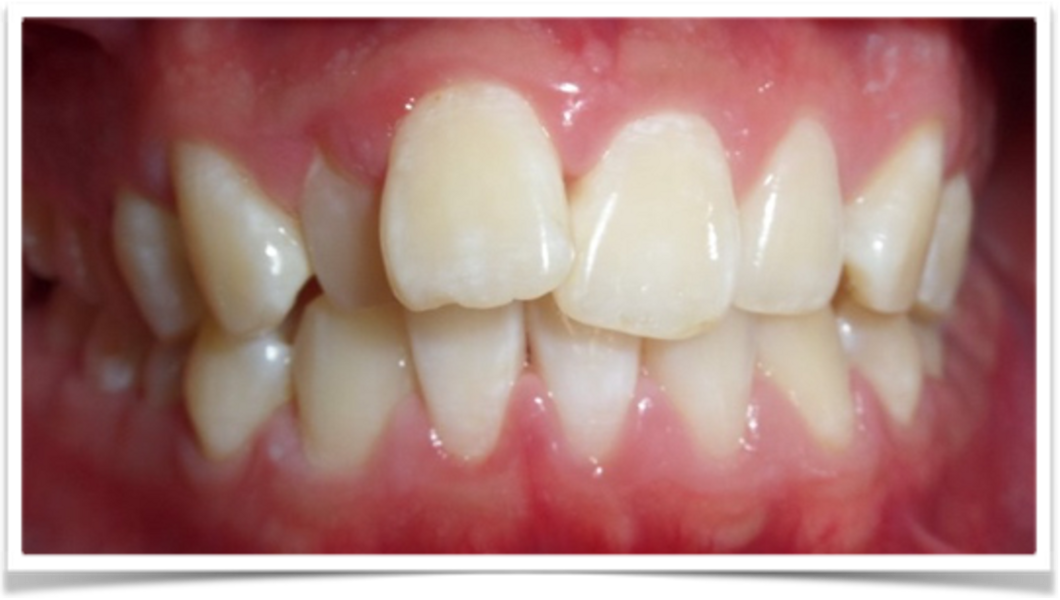

The patient presented with the goal of enhancing her smile. She had a narrow smile, bilateral posterior crossbite and an anterior crossbite with tooth #12. From the extra-oral perspective, the patient was also wider on the right vertical fifth (Figs. 25–28). The treatment objective was to correct the anterior crossbite and posterior crossbite and to simultaneously correct the asymmetrical buccal corridors by further broadening the arch on the right more than the left. Once the alignment had been completed, the case was finished with in-chair tooth whitening and composite augmentation of teeth #12 and 22 (Figs. 29–31).

The second case using VISS demonstrates the power of visualisation of a restorative solution, clear aligner solution or both. This technique predictably engages the patient to realise that it is not necessarily a decision of one or the other but both. The patient desired veneers and presented with an anterior crossbite of teeth #11 and 21, narrow teeth #12 and 22 in relation to teeth #11 and 21, asymmetrical buccal corridors and a gummy smile tendency (Figs. 38–41).

In collaboration with the clear aligner software and VISS, we provided the patient with choice and collaboration for both a restorative and orthodontic solution. We began with clear aligners first to balance the buccal corridors, creating space equally and symmetrically around teeth #12 and 22. This treatment was orthodontically established within ten months. VISS was then engaged to facilitate soft-tissue recontouring and a restorative solution on teeth #12 and 22 only versus soft-tissue recontouring and a restorative solution for the eight maxillary anterior teeth (Figs. 42 & 43). The patient proceeded with optimal tooth colour and shape via IPS e.max veneers on the eight maxillary anterior teeth after alignment and soft-tissue recontouring of the maxillary anterior teeth (Figs. 44–46).